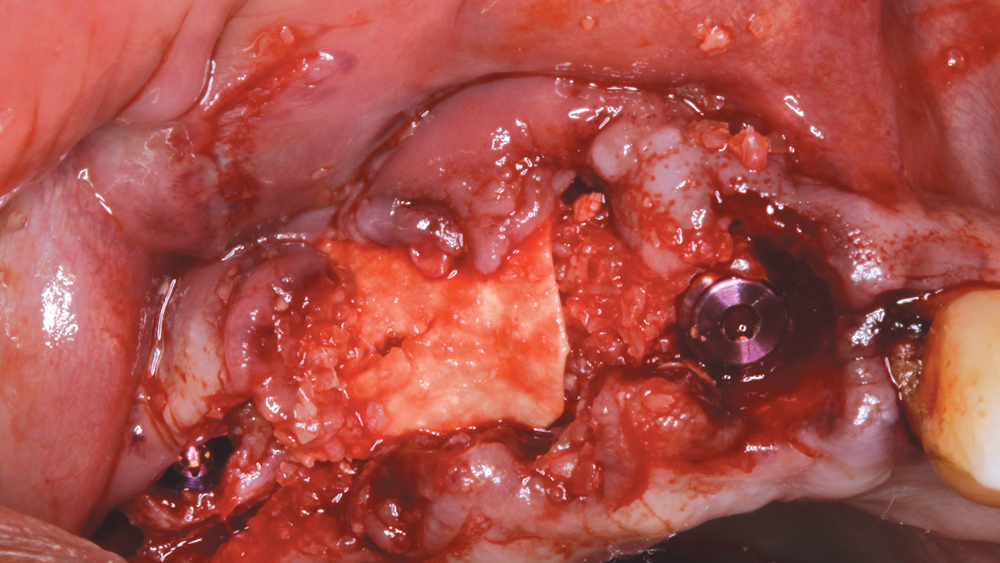

Ideal Implant Selection and Grafting of the Site

The Hahn™ Tapered Implant was chosen for Weldon because it is ideally suited for this type of case. For example, the pronounced threads excel in establishing initial implant stability in a fresh socket site. The machined collar helps to prevent bone loss around the neck of the implant and also has a cleansable surface. The prosthetic connection with built-in platform-switching helps to minimize the resorption that could occur with other systems, where the connection between the implant and abutment is at bone level, by preventing a microgap and potential bacterial invagination. And of course, the Hahn Tapered Implant System allows for either a cemented or screw-retained restoration.

After removing the untreatable teeth, I placed five Hahn Tapered Implants into the extraction sockets, grafted the area with Newport Biologics™ Mineralized Cortico/Cancellous Allograft Blend (Glidewell Direct) mixed with harvested autograft from the osteotomy sites, and used a Newport Biologics Resorbable Collagen Membrane 3-4 (Glidewell Direct) as a barrier against epithelial downgrowth during the healing and remodeling phase.